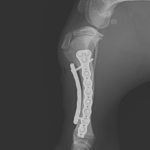

若齢犬の脛骨らせん状骨折

パピーがアクシデントで脛骨を骨折したとのこと。かかりつけ医から固定術の依頼がありました。長くらせん状に骨折ラインが確認されました。Titanium Locking Plateを使いオルソゴナル・ダブルプレート法で固定術を行いました。また、このワンコの脛骨の形状は特殊であり、近位の骨幅は広く確保できるのですが、骨幹部は湾曲が強くプレーティングには工夫が必要です。しばらく安静が必要ですがまたドッグランで走れるようになれます。